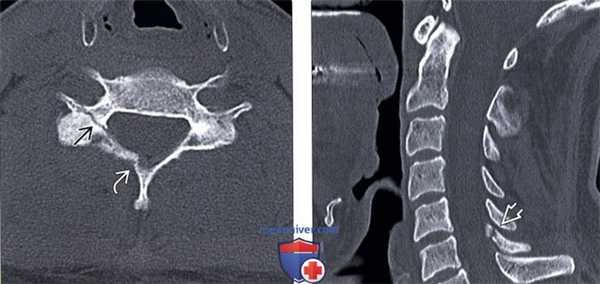

(Справа) Т2-ВИ, сагиттальная проекция: тяжелая флексионная травма шейного отдела позвоночника с подвывихом С5 позвонка, сгибательной деформацией, тяжелым сдавлением спинного мозга и его отеком. Обратите внимание на признаки разрыва задних связок. (Слева) КТ, сагиттальный срез с КУ: пациент с флексионной травмой шейного отдела позвоночника, нижний суставной отросток С6 располагается впереди верхнего суставного отростка С7 Б («сцепившийся вывих»).

(Справа) КТ, аксиальный срез с КУ: пациент с флексионной травмой шейного отдела позвоночника с «сцепившимся вывихом», нижние суставные отростки С6 располагаются впереди верхних суставных отростков С7 (такая рентгенологическая картина носит название признака «обнаженных фасеток» или признака «гамбургера»).